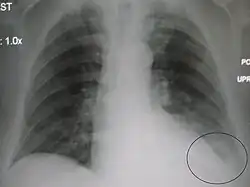

AP CXR showing left lower lobe pneumonia associated with a small left sided pleural effusion -

AP CXR showing right lower lobe pneumonia -

AP CXR showing pneumonia of the lingula of the left lung -

Left upper lobe pneumonia with a small pleural effusion.